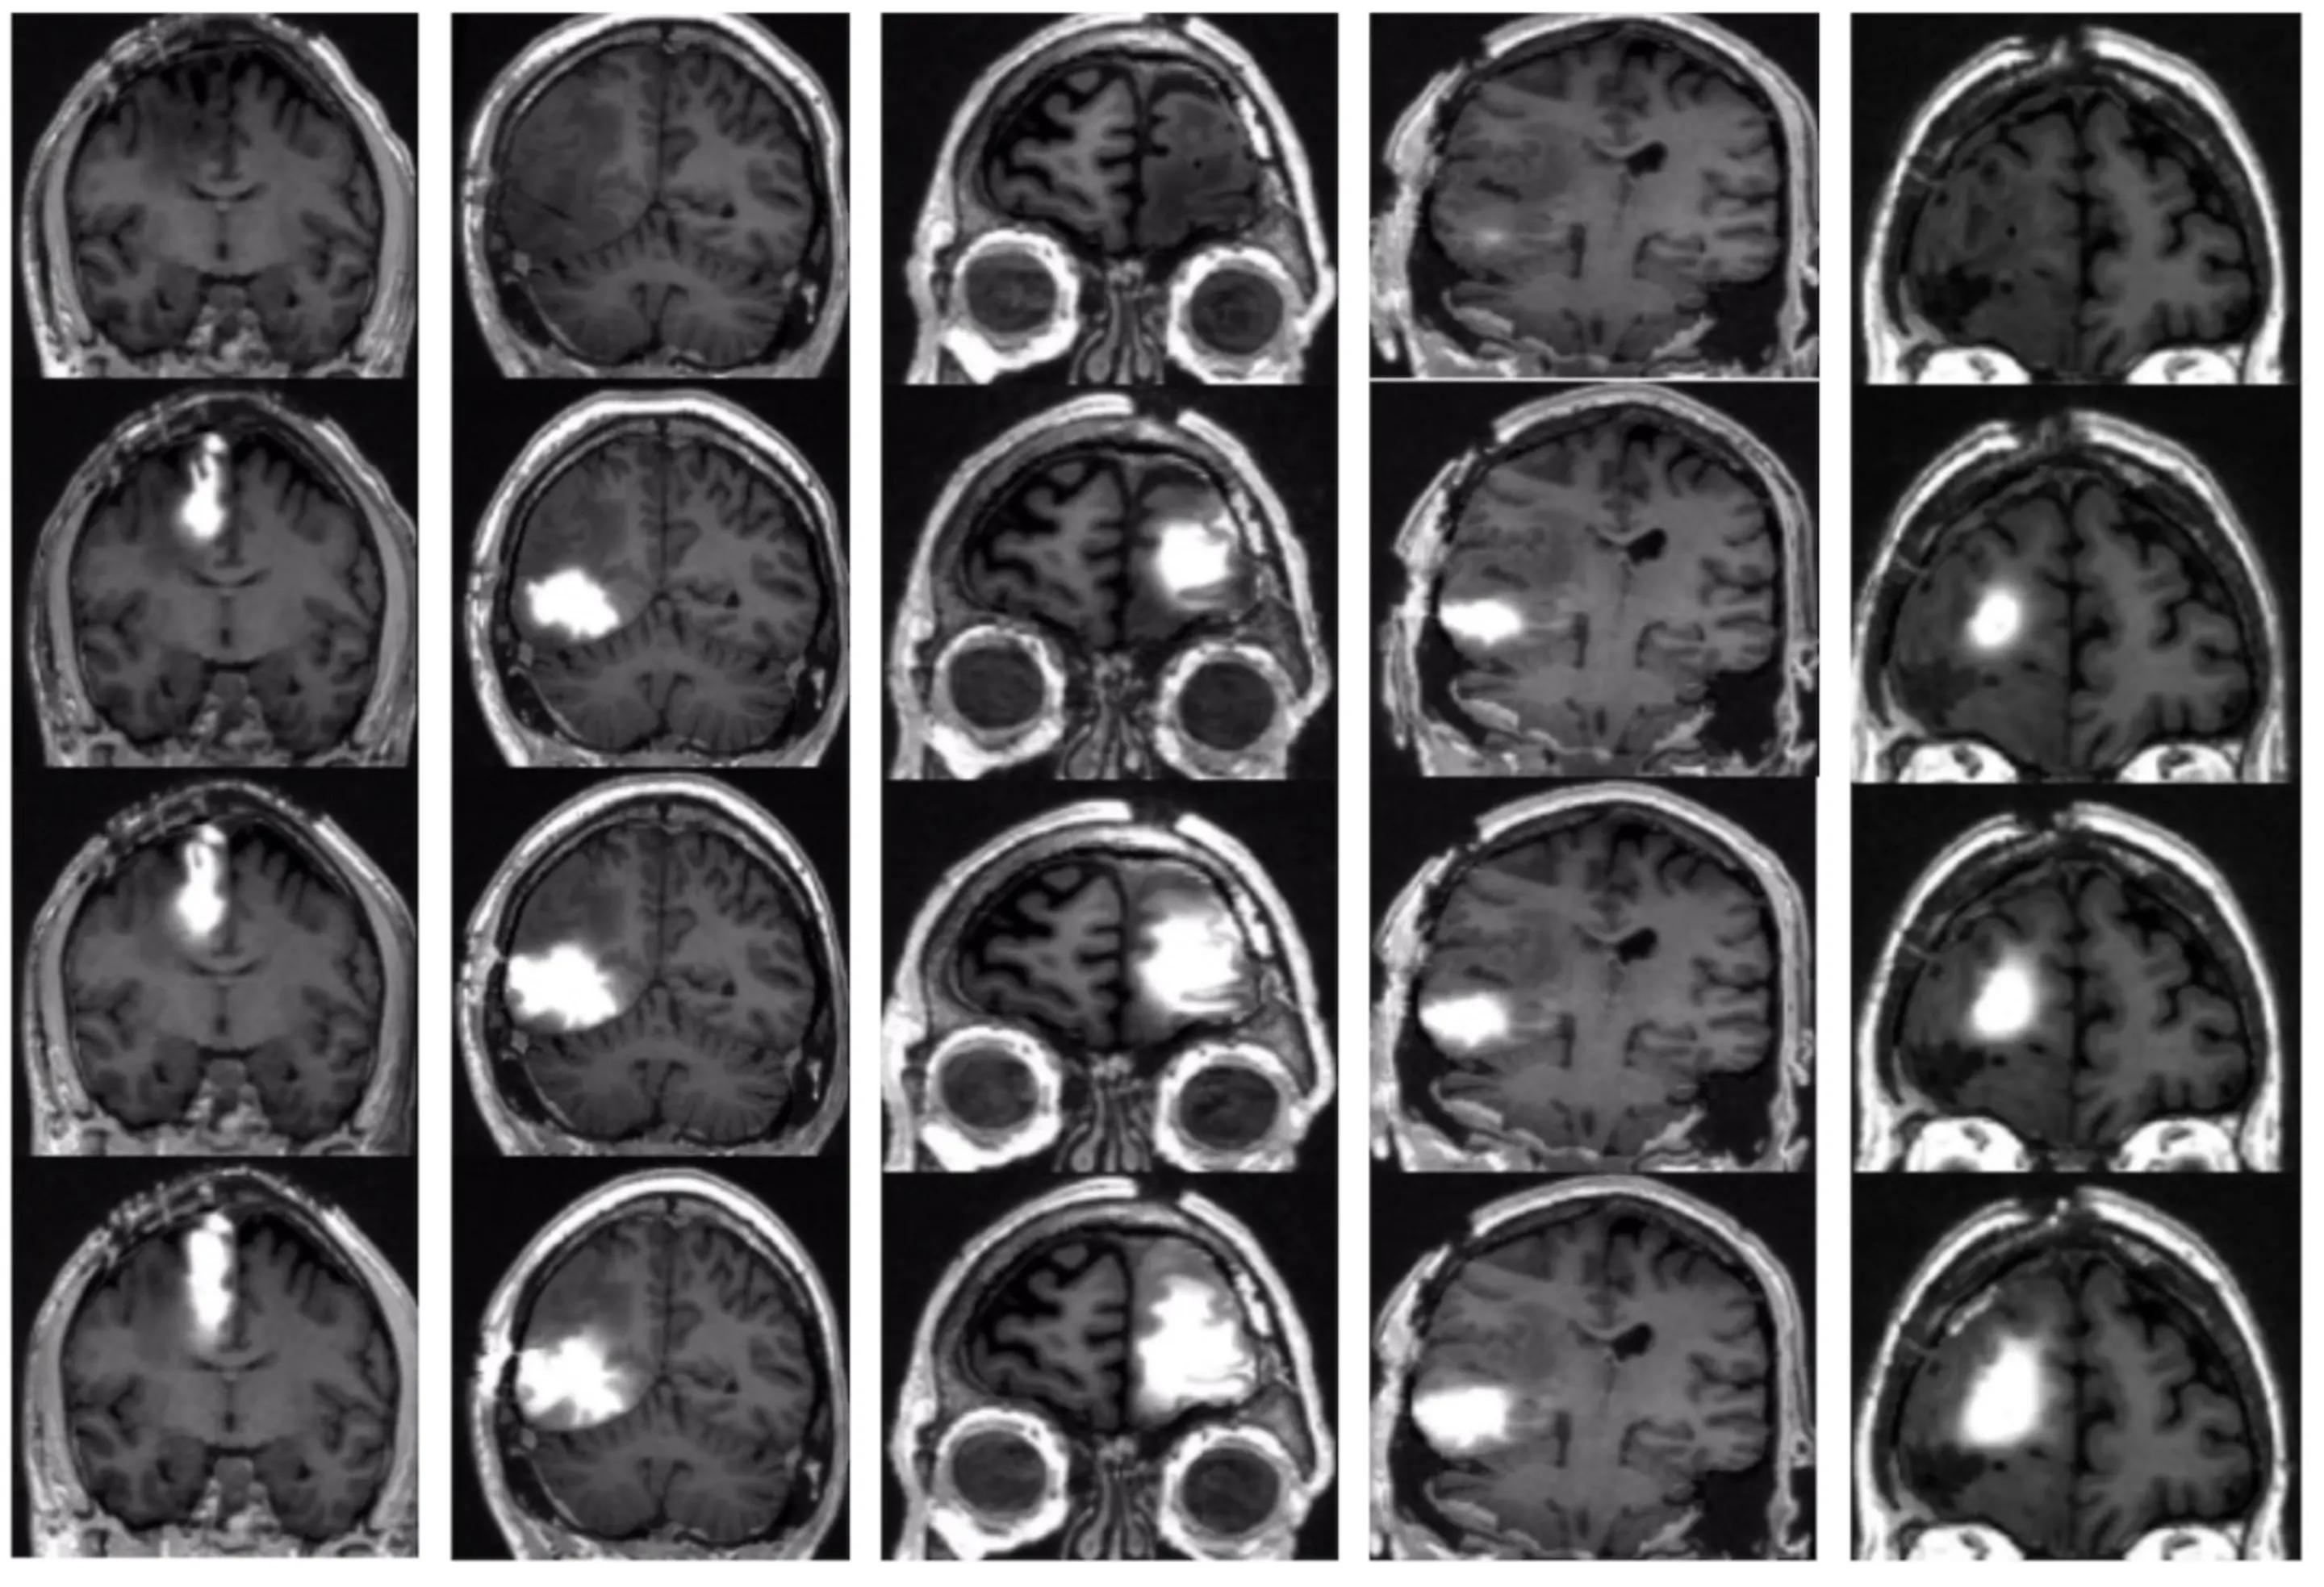

五名患者的脑部扫描,在治疗前(从上到下),以及治疗后14、24和48小时,显示了他们肿瘤周围的化疗药物浓度。图/杰弗里-布鲁斯 哥伦比亚大学欧文医学中心

在人体试验中,五名复发性胶质母细胞瘤患者接受了这种泵的植入,它输送化疗药物拓扑替康以及一种称为钆的追踪剂,因此科学家们可以测量药物的浓度和分布。患者连续接受了四次为期一周的治疗,泵开启两天,关闭五天。

治疗后几天的核磁共振扫描显示,化疗药物成功饱和了肿瘤和周围区域。治疗后的活组织检查显示,活跃的肿瘤细胞数量明显减少,而没有影响健康的脑组织。而且重要的是,没有病人出现严重的神经系统并发症。